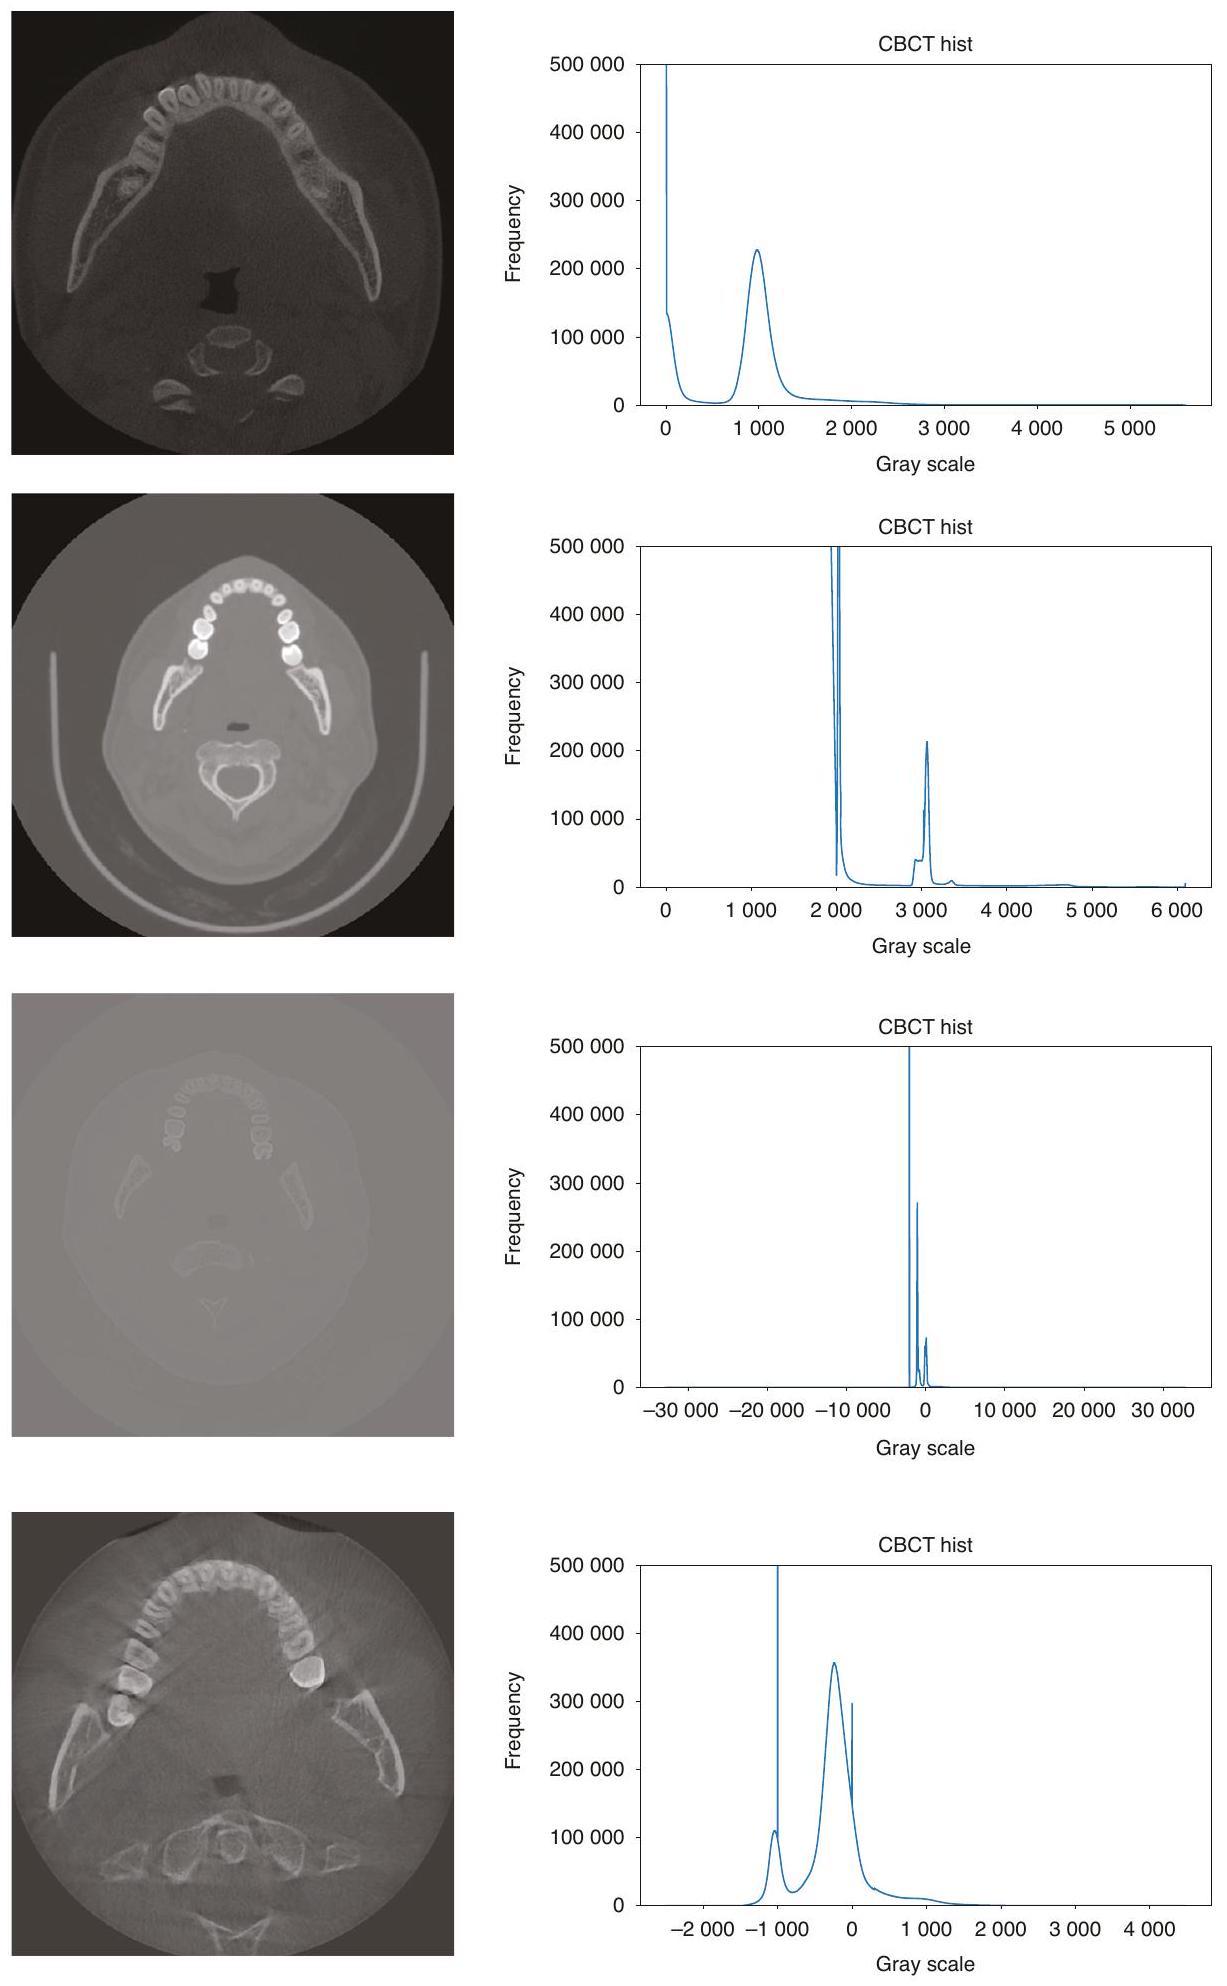

طرق المعالجة المسبقة لجميع صور CBCT؛ وفي مهمة تقسيم الأسنان، فإن معظم الصور الأصلية هي مناطق أنسجة لينة غير مفيدة للتقسيم، مما يؤدي إلى توزيع غير متوازن للبيانات، وهو ما لا تعالجه الطرق الحالية. تُظهر الصور الفعلية لـ CBCT في الشكل 2، ويمكن ملاحظة وجود اختلافات كبيرة في تباين الصورة، ومجال الرؤية، وما إلى ذلك. - الطرق الحالية معقدة للغاية وغالبًا ما تتطلب خطوات متعددة للحصول على نتائج تقسيم جيدة. قد تتطلب هذه الطرق استخدام تقنيات معالجة مسبقة متعددة، وطرق استخراج الميزات، والمصنفات أو النماذج، وخطوات المعالجة اللاحقة لإكمال تقسيم الأسنان. تؤدي هذه التعقيدات إلى طرق أقل كفاءة من الناحية الحسابية، حيث قد يقدم كل خطوة أخطاء أو عيوب، وكل خطوة في العملية الكاملة تتطلب ضبطًا دقيقًا وتحققًا، مما يزيد من صعوبة تطوير الطرق وتطبيقها.

preprocessing methods to all CBCT images; and in the tooth instance segmentation task, most of the original images are soft tissue regions that are not useful for segmentation, resulting in an unbalanced distribution of data, which is not addressed by the current methods. The actual CBCT images are shown in Fig. 2, and it can be seen that there are large differences in image contrast, field of view, etc. - Existing methods are too complex and often require multiple steps to obtain good segmentation results. These methods may require the use of multiple preprocessing techniques, feature extraction methods, classifiers or models, and post-processing steps to complete the segmentation of teeth. This complexity leads to less computationally efficient methods, each step may introduce errors or mistakes, and each step in the whole process requires careful tuning and validation, which increases the difficulty of method development and application.